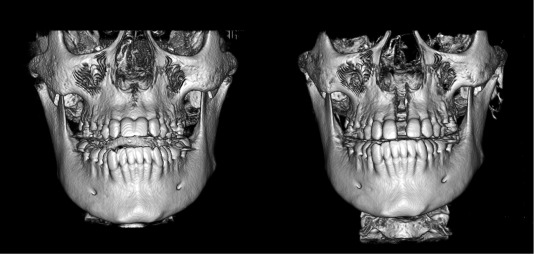

View attachment 4683044

Found this photo off google but you can see in the second photo the zygos are way more prominent after the maxilla has been expanded. Don't have any b4 and after photos of my friend but I can say first hand MARPE did improve his zygos, and if ur cool with having a tooth gap for a couple months feel free to try it.